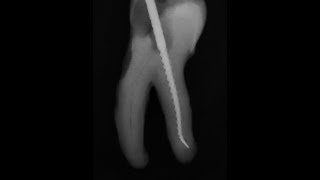

Как закрыть перфорацию зуба? Перфорация корня зуба. Что такое перфорация зуба